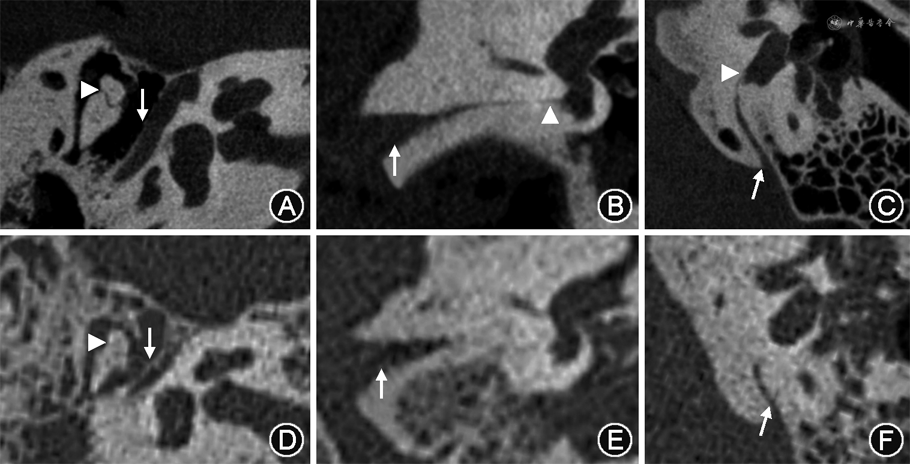

对比U-HRCT(100 kV、120 mAs组)和MSCT(120 kV、310 mAs组)的颞骨图像可以看出,U-HRCT整体图像质量明显优于MSCT(图1);U-HRCT对锤砧关节(图1A)、面神经管骨壁(图1A)、耳蜗导水管内口(图1B)、前庭导水管内口(图1C)等精细结构显示清晰。

U-HRCT图像主观评分和CNR均优于MSCT[5.00(4.25,5.00)比4.00(3.00,4.00),10.26±1.38比5.48±0.22,P<0.001](表5),有效剂量是后者的1/3(82.99 μSv比252.56 μSv),FOM是后者的11.16倍(1 268.44 mSv-1比113.71 mSv-1)。